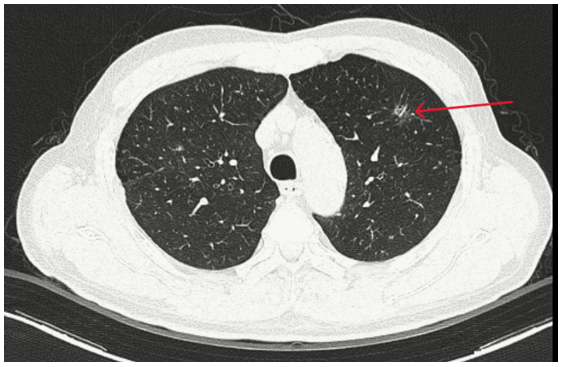

- Chụp CT ngực: Hình ảnh đám tổn thương kính mờ có bờ tua gai thùy trên phổi trái

Hình 1 : Thùy trên phổi trái có đám tổn thương kính mờ, bờ tua gai kích thước 10x13mm.